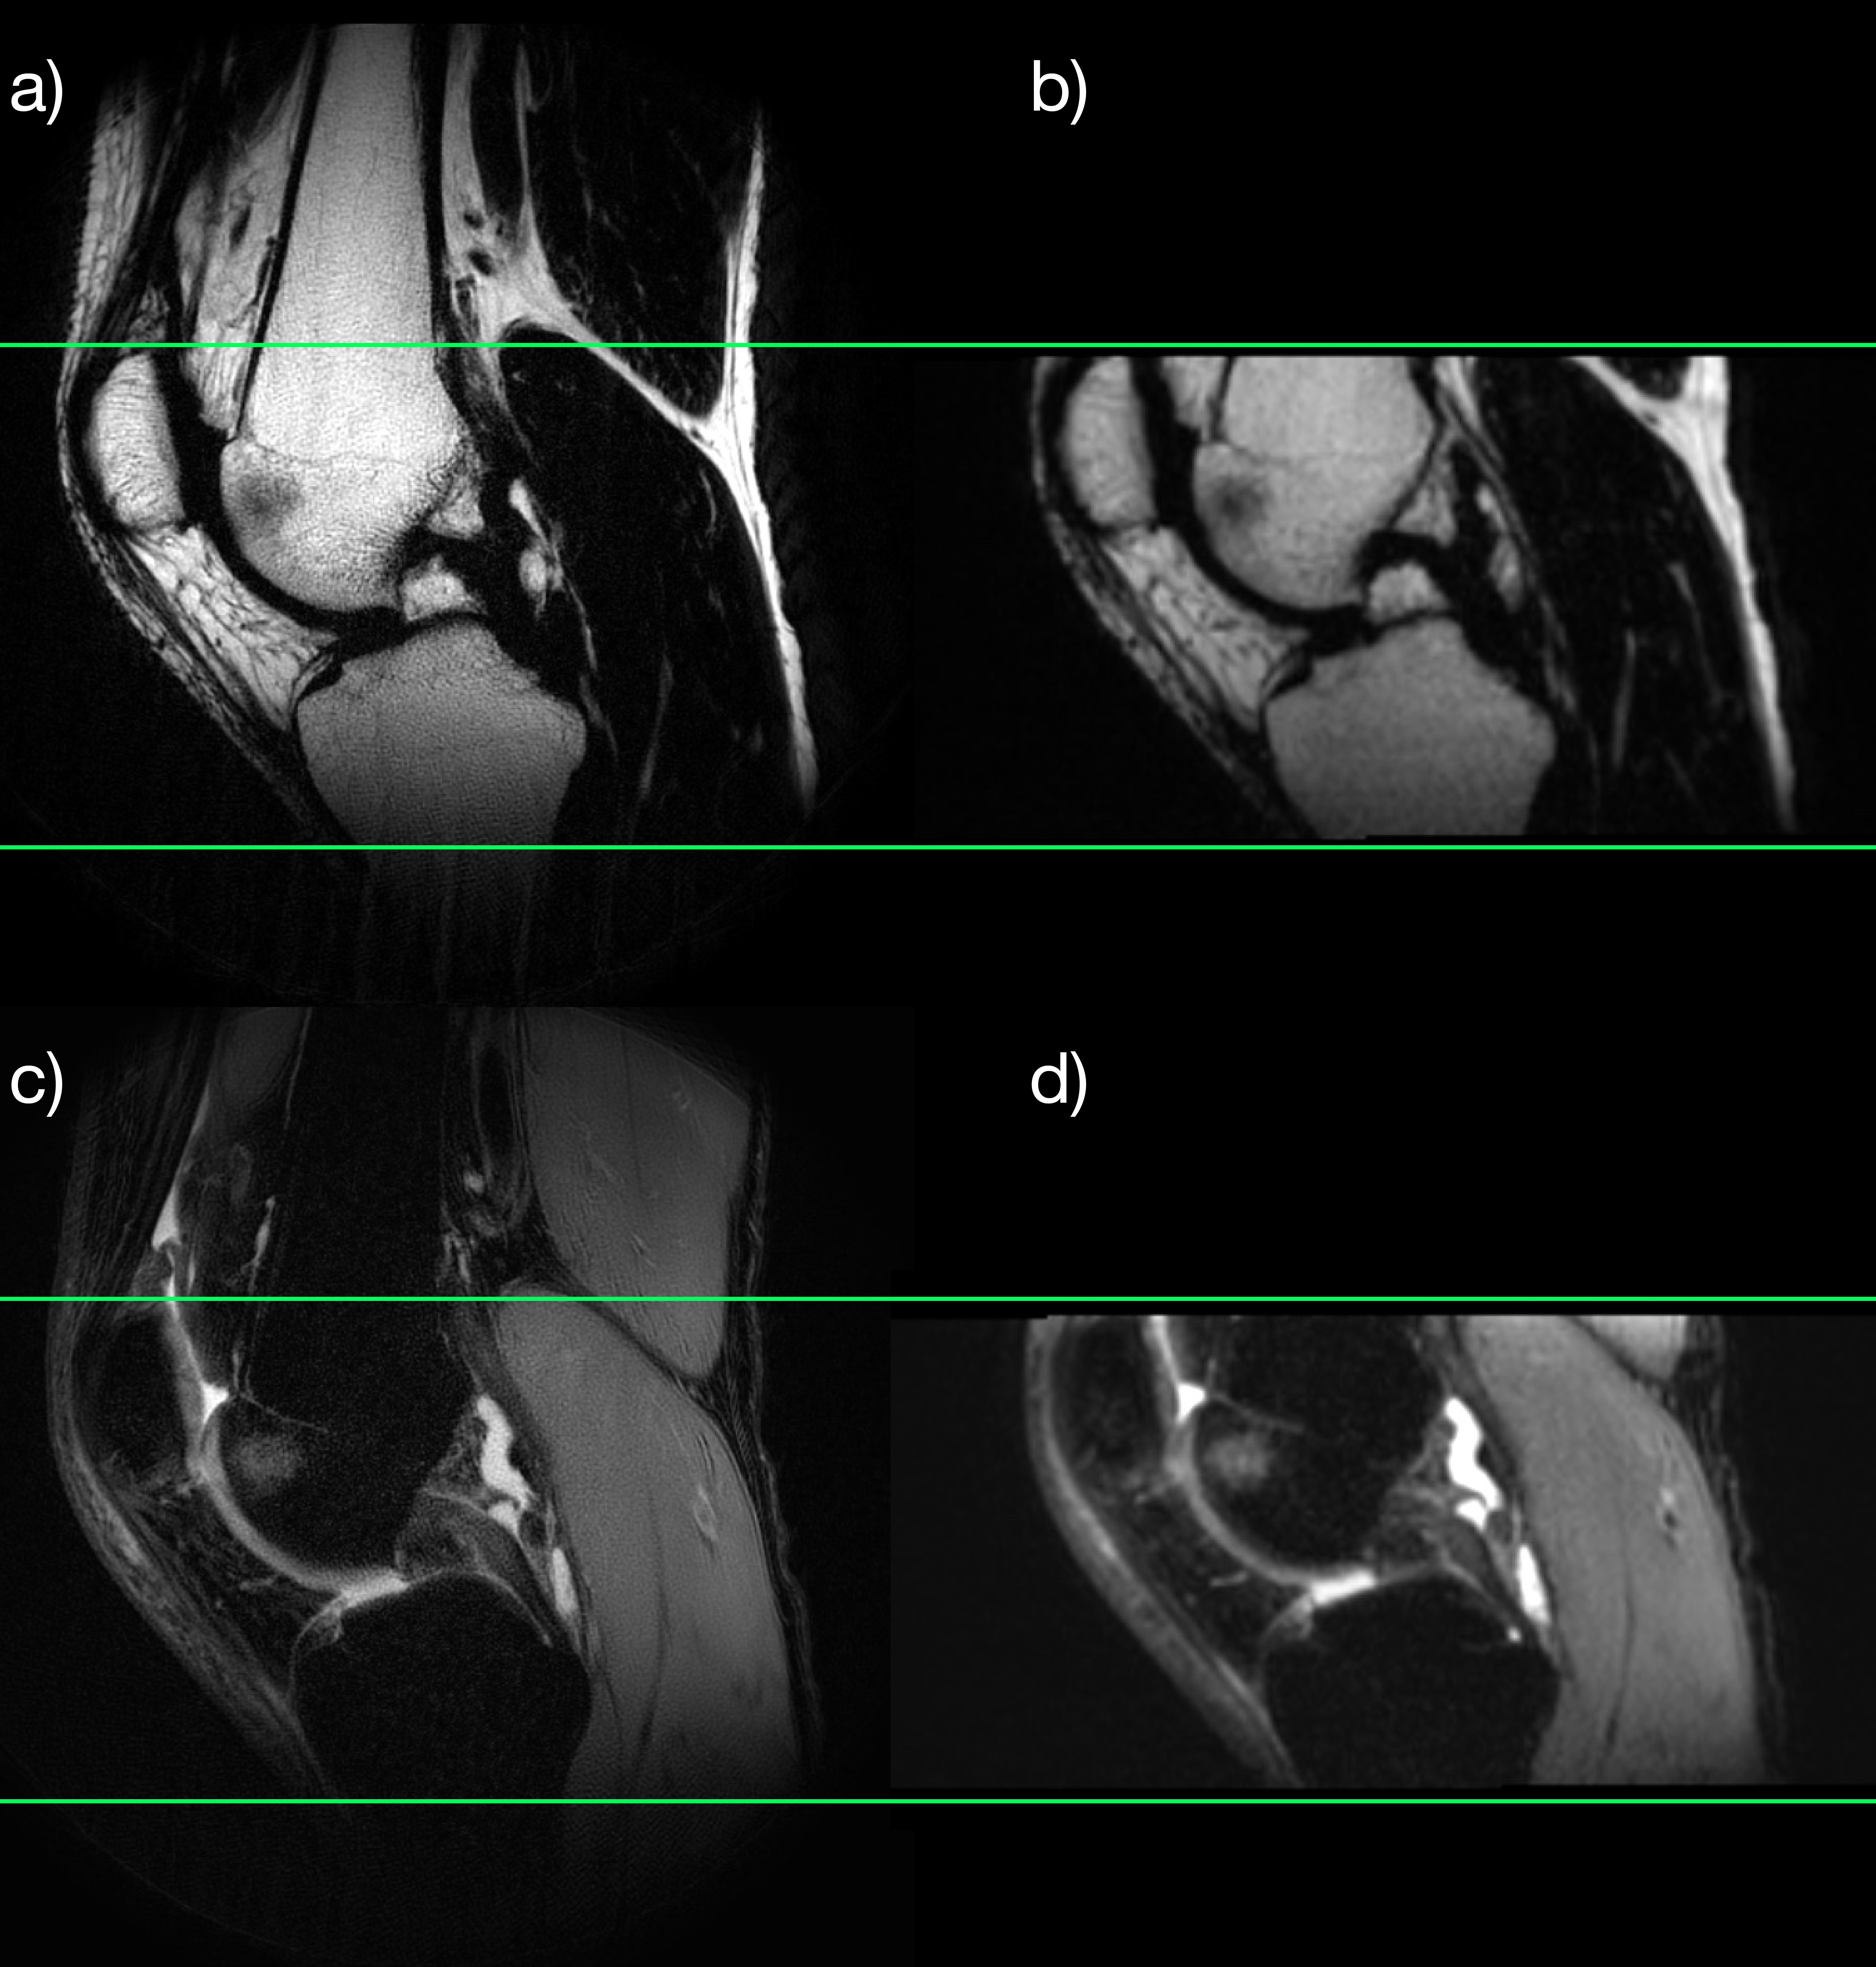

Figure 2: Right knee. Fat/water separated pseudo 3D PROPELLER images with coronal and sagittal reformats. Displaying the fat images in the top row (a-c) and the water images in the bottom row (d-f). Green lines show the positions of corresponding image planes. The bone marrow edema (pointed out by the green lines) is bright on the water images and dark on the fat images.